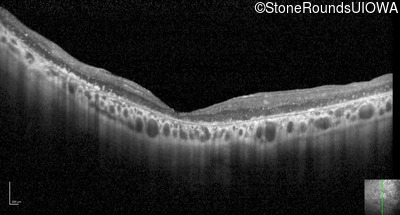

Optical Coherence Tomography - Right - 20/250 sc

Exemplar / OCT Stack

OCT Stack